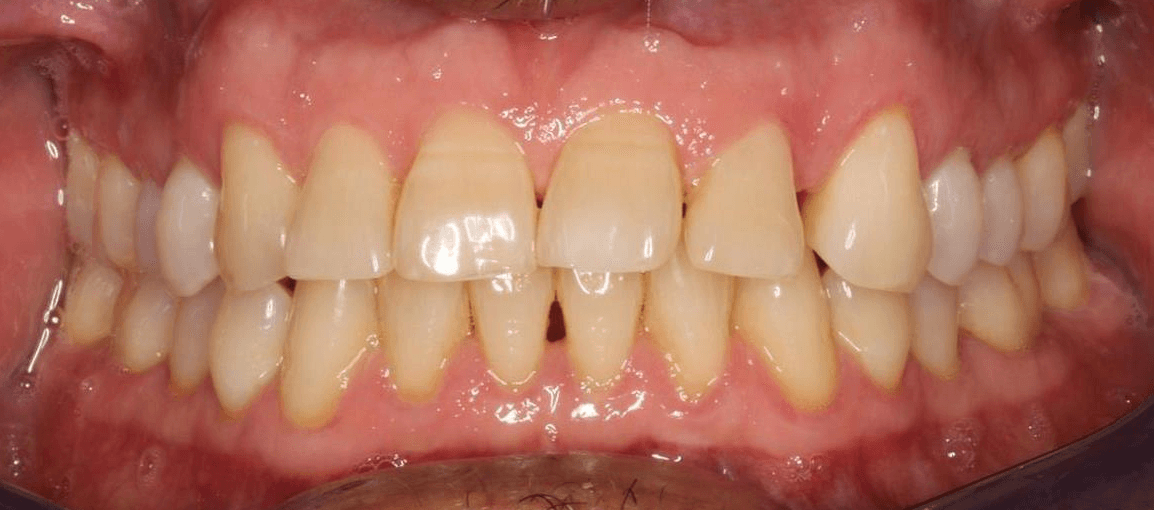

Diganosis: A mix of crowding and mild spacing, moderate curve of Spee, black triangles, significant overjet, reverse smile display

Final results

INTRAORAL